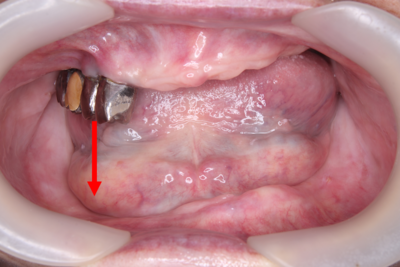

お口の中の写真を見るとやはり向かって左下が凹んでいます。それに対して、上あごにご自分の歯が4本残っています。

向かって左下が凹んでしまった理由として考えられることのひとつは、しっかりと残っている上の歯がハンマーの様に下の入れ歯を叩くので、どんどん凹んでしまった可能性があります。非常に難しい症例です。

また上の歯が矢印のように噛んでくると下の歯は内側ではなく外側に並んで噛ませないといけませんので、交叉咬合(※)といわれる噛み合わせになります。これは入れ歯の噛み合わせとしては、バランスを保てないので難しくなります。